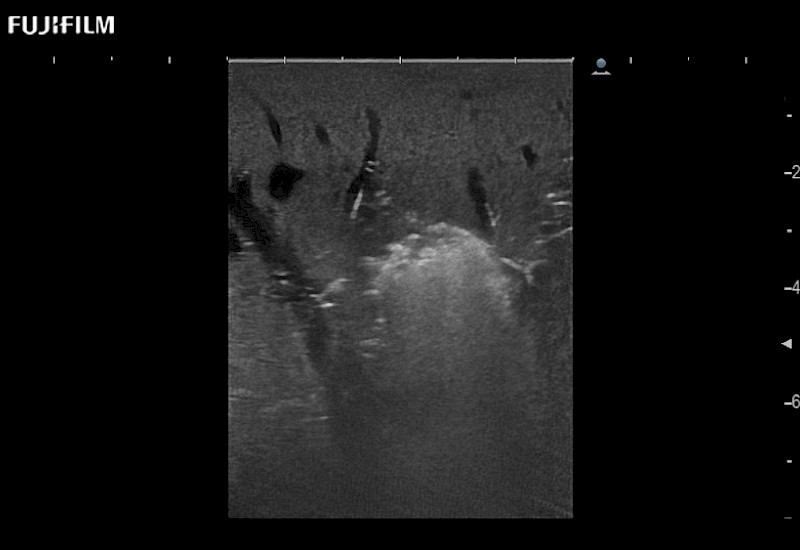

Extraordinary high-resolution digital imaging

- Exceptional near and far-field resolution

- Instant feedback on tumor margin delineation

- Valuable information to guide tumor resections

- Exceptional near and far-field resolution

- Instant feedback on tumor margin delineation

- Exceptional near and far-field resolution

- Exceptional near and far-field resolution

- Instant feedback on tumor margin delineation

- Exceptional near and far-field resolution

- Instant feedback on tumor margin delineation

- Exceptional near and far-field resolution

- Instant feedback on tumor margin delineation

- Exceptional near and far-field resolution

- Instant feedback on tumor margin delineation

- Valuable information to guide tumor resections

- Exceptional near and far-field resolution

- Instant feedback on tumor margin delineation

- Valuable information to guide tumor resections

- Exceptional near and far field resolution

- Instant feedback on tumor margin delineation

- Valuable information to guide tumor resections

- Exceptional near and far-field resolution

- Instant feedback on tumor margin delineation

- Valuable information to guide tumor resections

- Exceptional near and far field resolution

- Instant feedback on tumor margin delineation